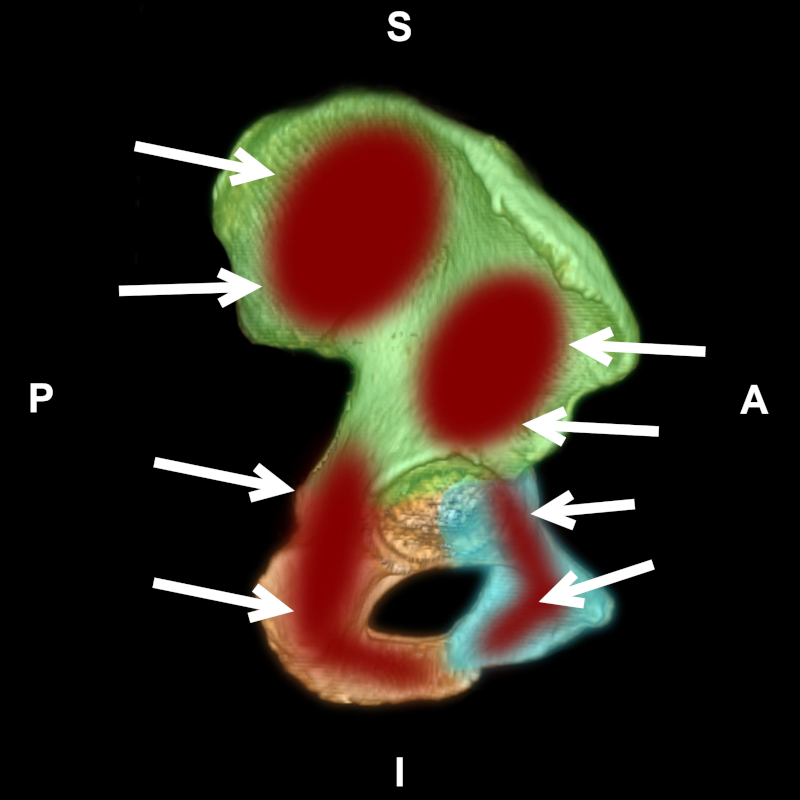

Figura 5

TC con reconstrucción 3D de pelvis, vista sagital. Huesos ilíaco (verde), isquion (naranja) y pubis (celeste). En rojo, lesiones óseas y sus vías de abordaje (flechas).